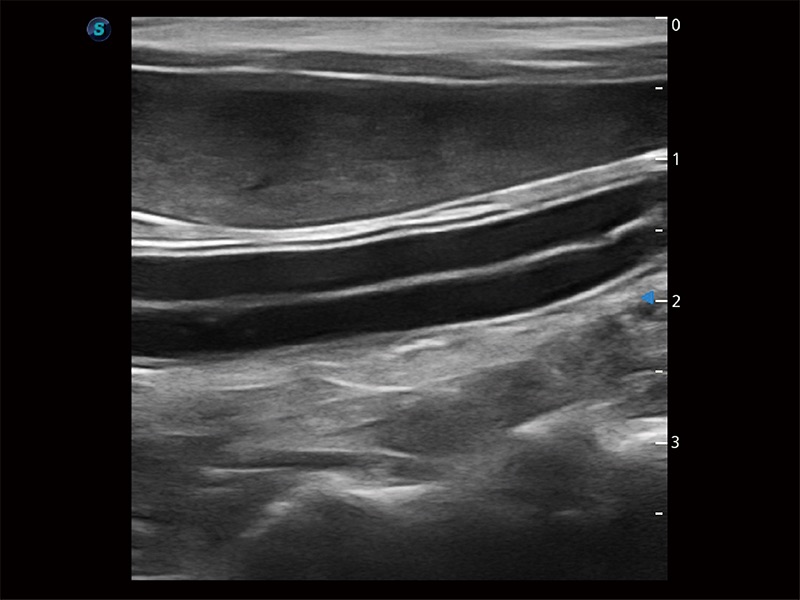

為精細(xì)結(jié)構(gòu)及組織邊緣提供高清晰度的圖像和更大的成像視野。幫助減輕醫(yī)生的用眼疲勞,快速精準(zhǔn)獲得測(cè)量的數(shù)據(jù)。

ProPet 80 全新的動(dòng)物超聲智能軟件和豐富的探頭群,為動(dòng)物醫(yī)生提供了高清晰度和精細(xì)分辨率的圖像,無(wú)論在寵物、馬科、畜牧還是實(shí)驗(yàn)室動(dòng)物等應(yīng)用中都可以輕松應(yīng)對(duì),為您的日常工作帶來(lái)滿意的體驗(yàn)。